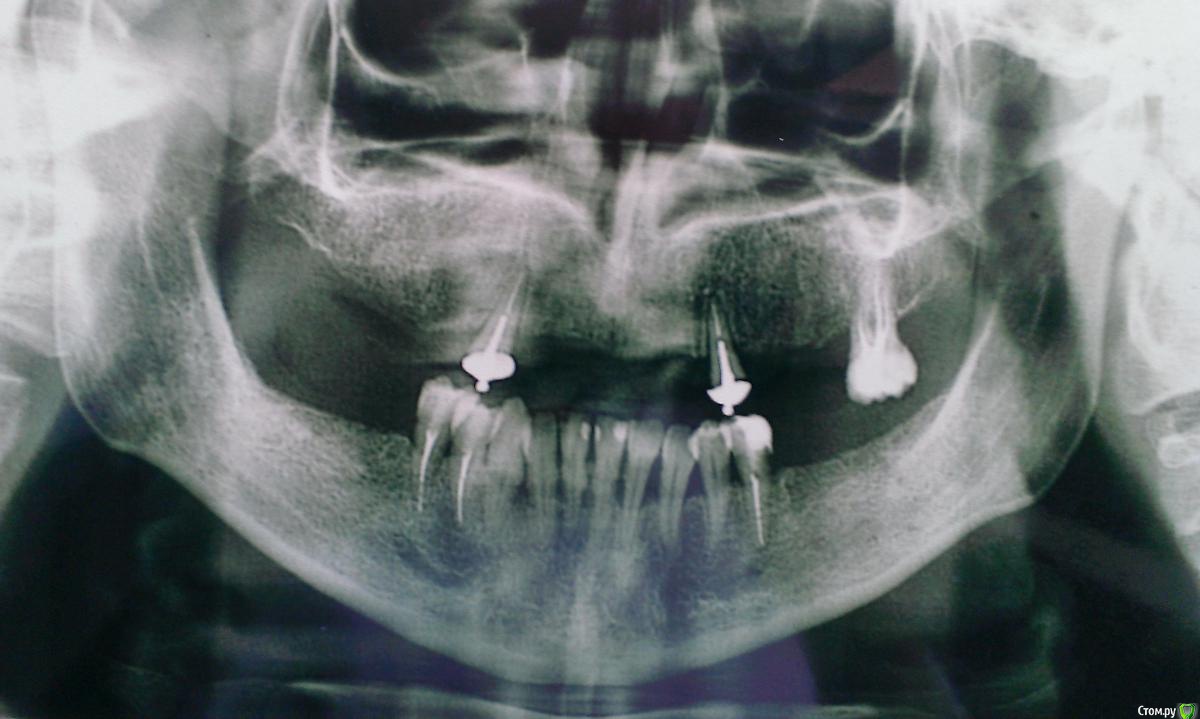

alekcandr ovs. Опубликовано 24 сентября, 2015 Поделиться Опубликовано 24 сентября, 2015 Пациентка 47 лет,мезиальный прикус,готова на имплантацию,извините что только ортопант...снимок.По финансам больше 8 имплантов не потянет,хочет несъемною конструкцию 1.закончить зубные ряди 6 зубами,и закрутить больше винтов на В/Ч????. 2.Будет ли достаточно 6 имплантом для несъёмной конструкции на В/Ч ???Подскажите пожалуйста по плану протезирования !!!! Ссылка на комментарий

Чертков Александр Опубликовано 25 сентября, 2015 Поделиться Опубликовано 25 сентября, 2015 1. Сделать каппу навигатор2. Удалить зубы в/ч3. Установить 6 имплантата ( я бы установил 6-4-2, 2-4-6)...постараться достичь необходимого торка 4. Интраоперационно снять оттиск для изготовления временной конструкции (винтовая фиксация, желательно армированная...в зависимости от возможностей Вашей лаборатории)5. Установить временную конструкцию в неотдаленные сроки (хотя это принципиального значения не имеет, главное формирователи при операции "до одури" не затягивать)6. По факту остеоинтеграции - изготовление постоянной конструкции (в любом удобном формате: винтовая, цементируемая...) Я бы сделал цельную (подкову), но тут вопрос "веры". Каркас хоть фрезеруемый, хоть литой (если литьё "вменяемое") 1 Ссылка на комментарий